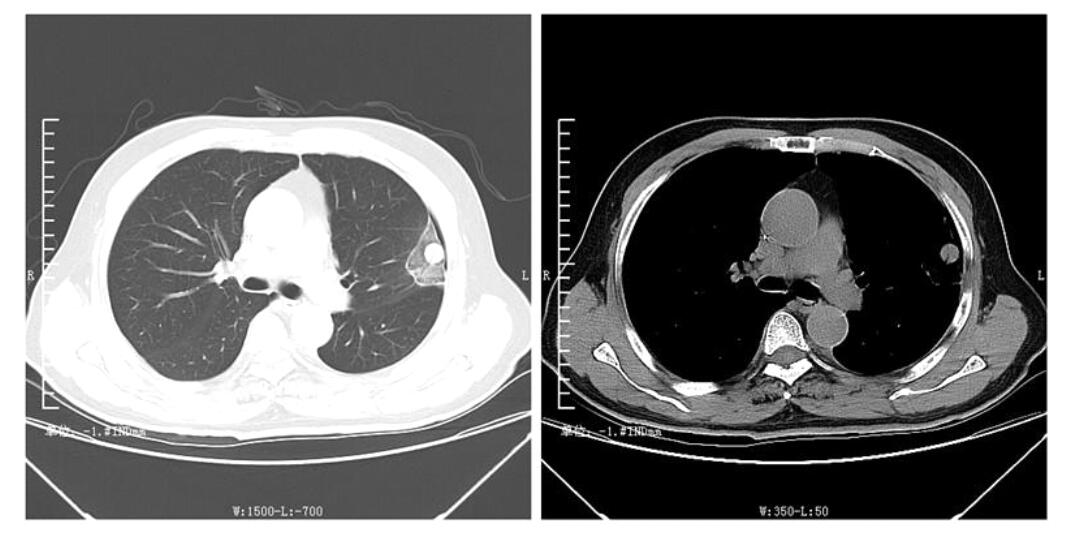

接下来让我们看一下患者的术中CT:

首次手术患者15天后复查的CT:肺内转移结节已被消融范围全面包裹,理论上包裹范围内肿瘤将全面失活(如下图)。